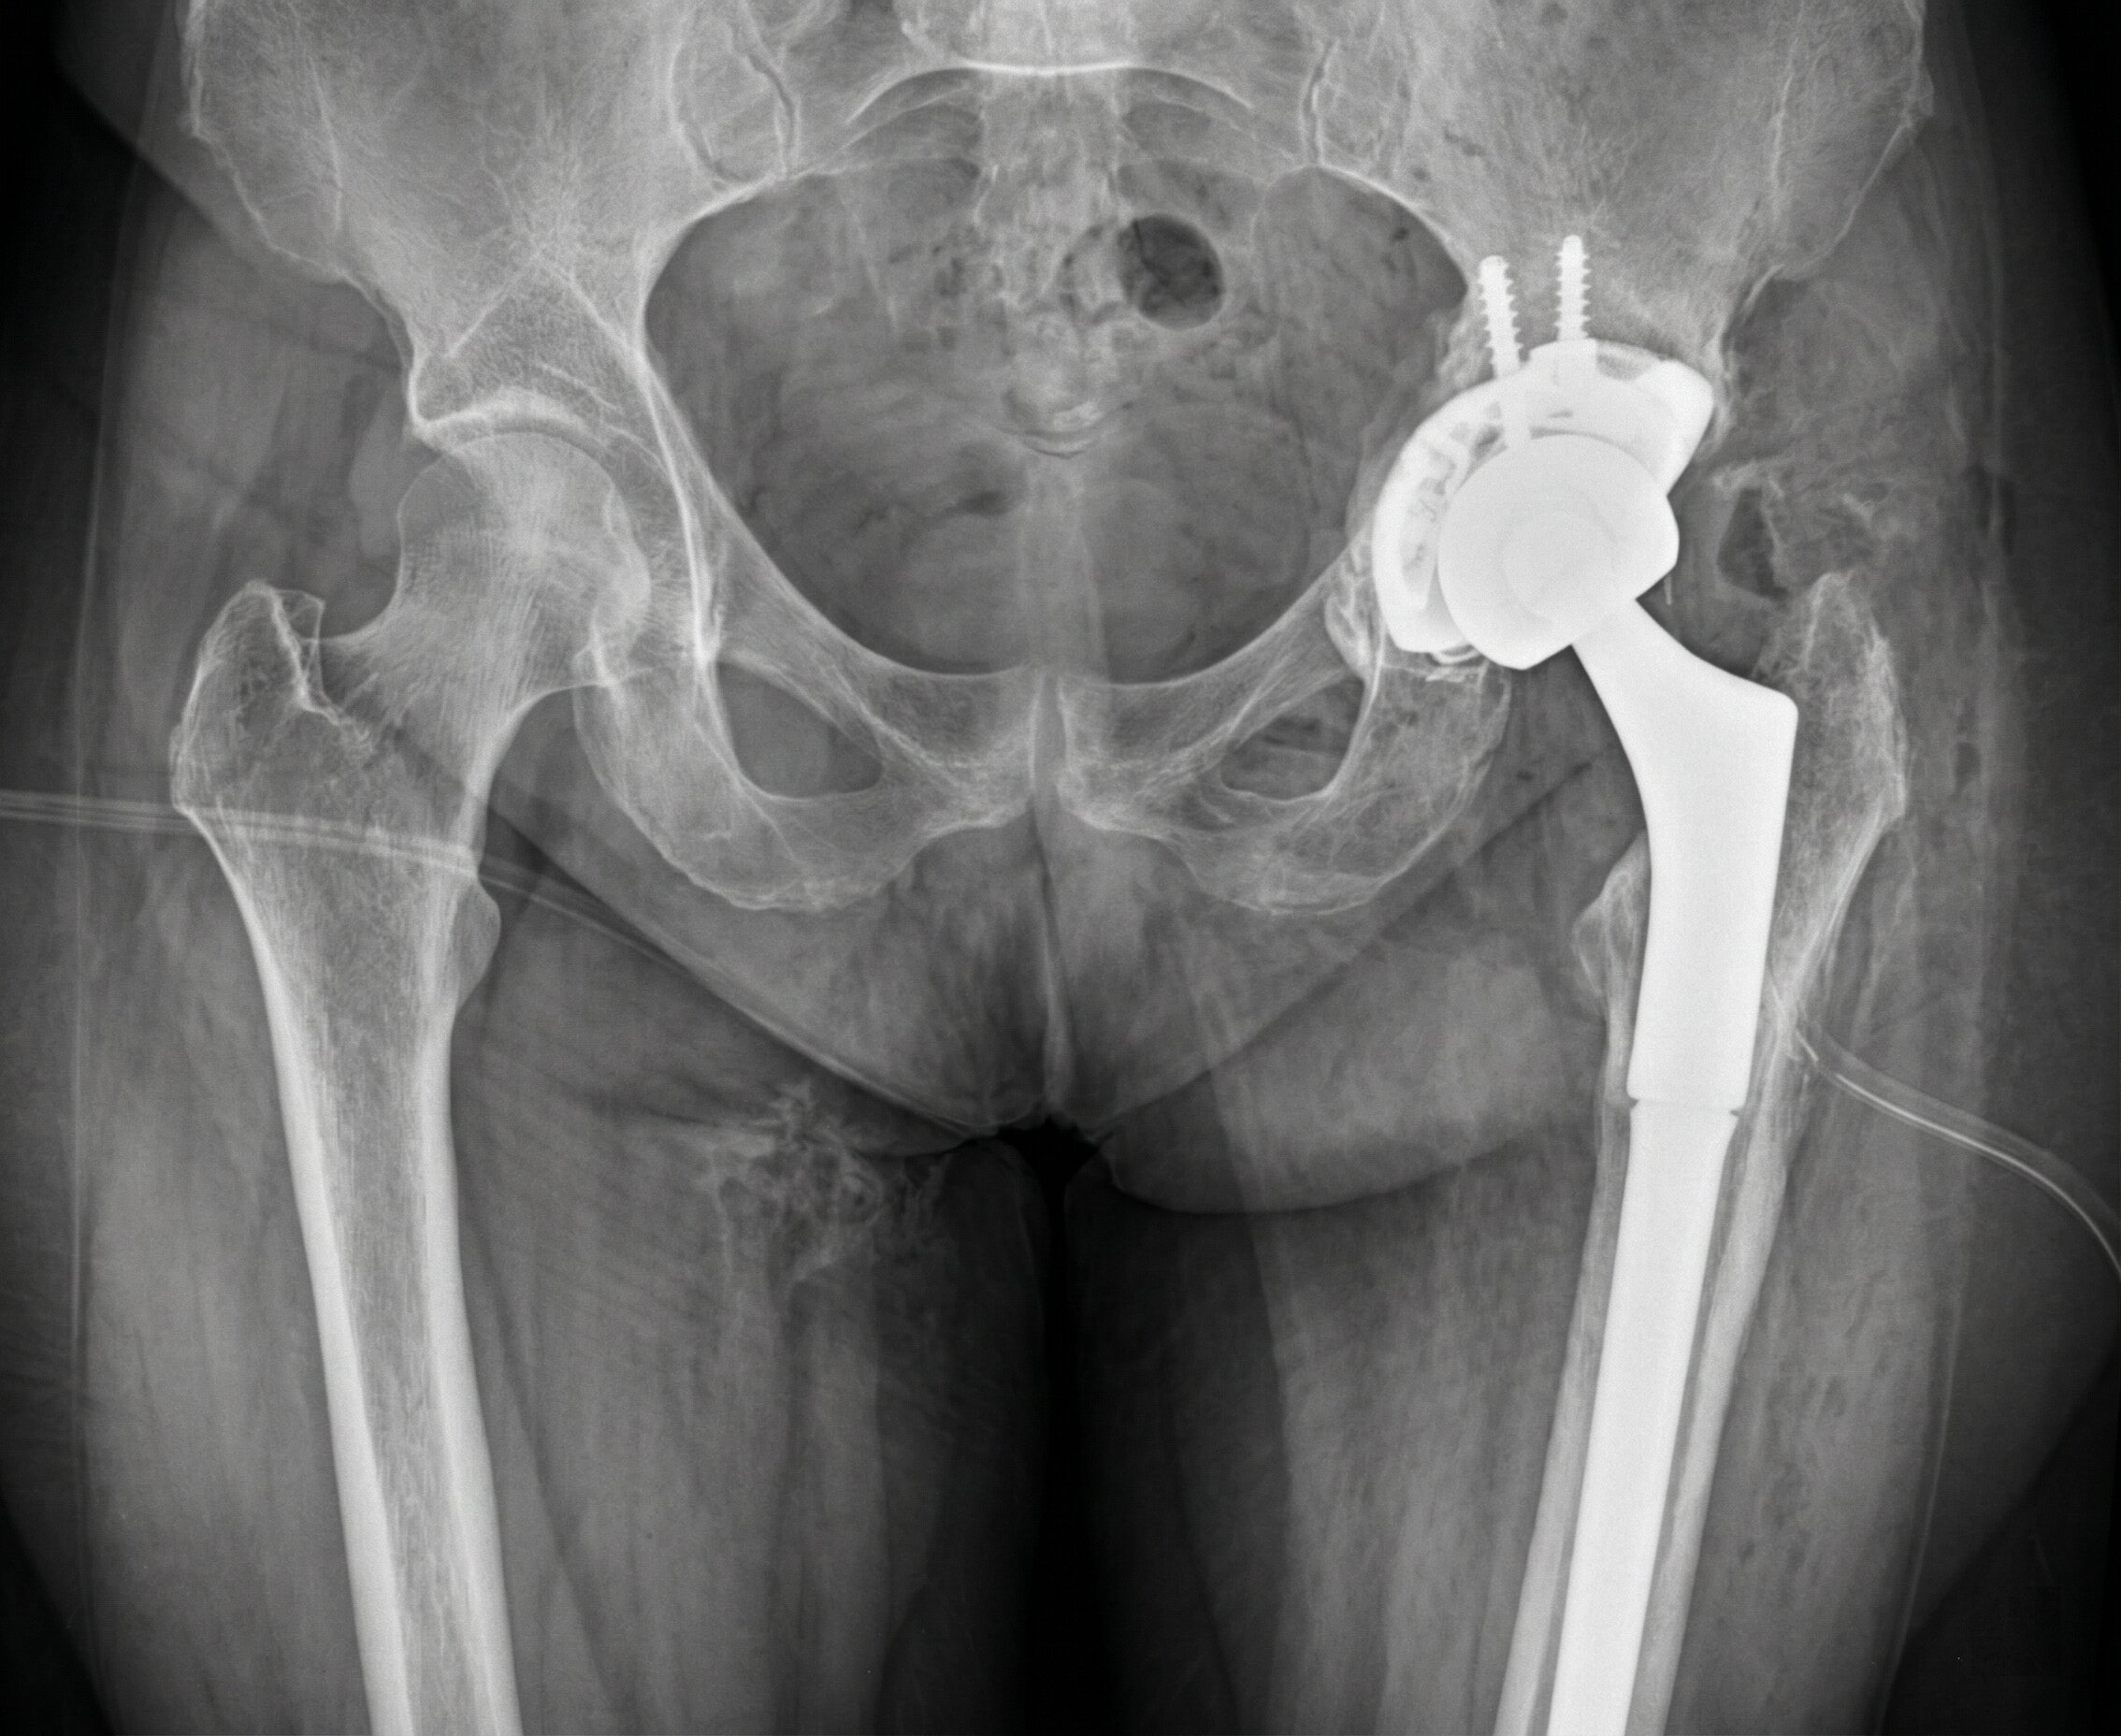

Infezioni Protesiche: Revisione

Si tratta di complicanze importanti caratterizzate da dolore, tumefazioni e segni infettivi.

Il trattamento è quasi sempre chirurgico associato a terapia antibiotica, spesso in più fasi e può richiedere la completa sostituzione dell’impianto.